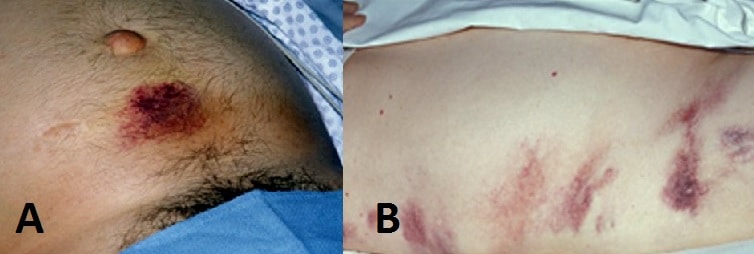

Less common signs that are often described are Cullen’s sign (bruising around the umbilicus, FIg. 2A) and Grey Turner’s sign (bruising in the flanks, Fig. 2B) , representing retroperitoneal haemorrhage. Tetany may occur from hypocalcaemia (secondary to fat necrosis) and, in select cases, gallstone aetiology may also cause a concurrent obstructive jaundice.